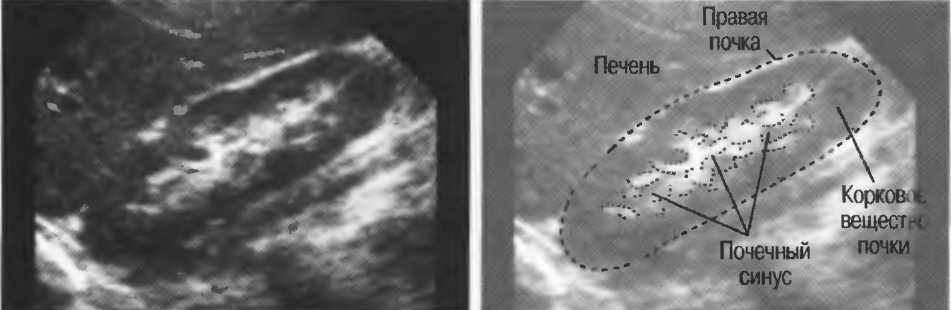

4. У здоровых обследуемых паренхима печени должна быть немного более эхогенна. чем кора рядом расположенной почки (рис. 26).

Рис.26. Продольный срез через печень и правую почку: нормальная паренхима печени более эхогенна, чем паренхима нормальной почки. Это еще один способ проверки качества изображения.